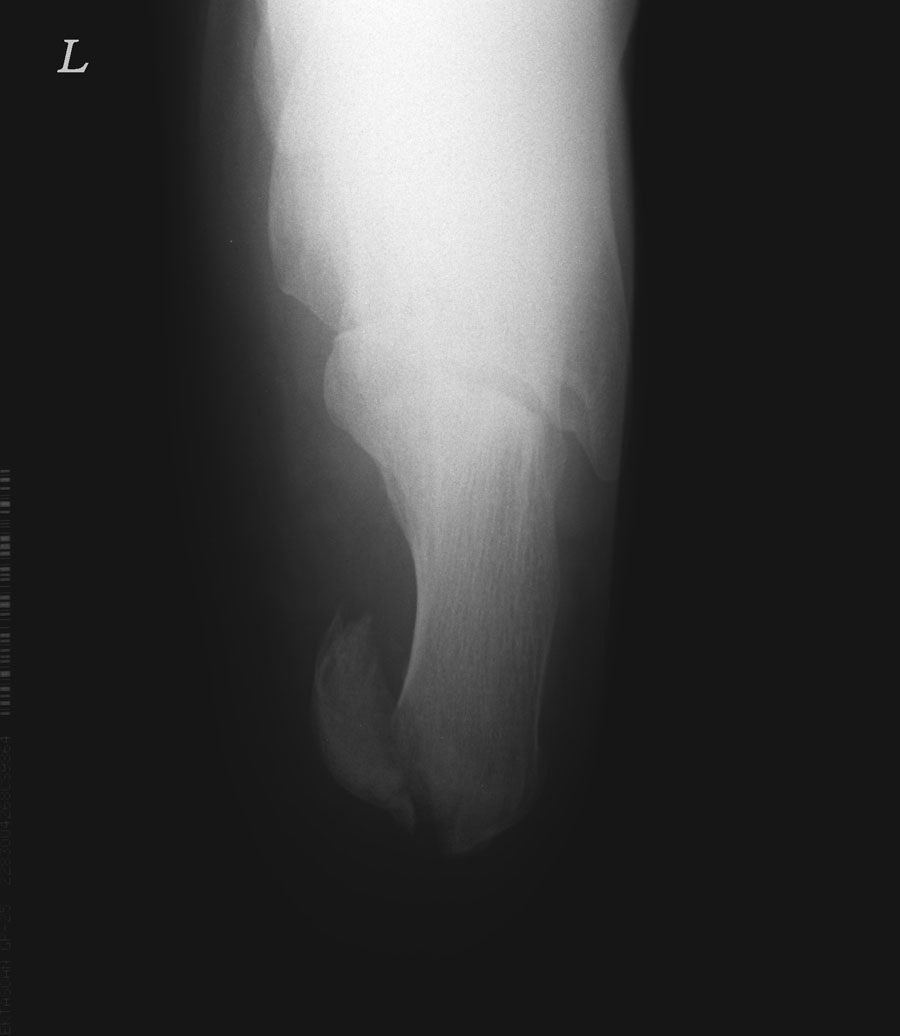

标题: X6651:跟骨骨折。

临床上开不来申请单,读不懂报告单的医生在基层医院比比皆是。我们常常见到跟骨骨折或第5跖骨基底部骨折而要求放射科照踝关节的。如果我们观察不仔细的话,这些骨折漏诊可能性就大了。本例便是。传跟骨轴位片。